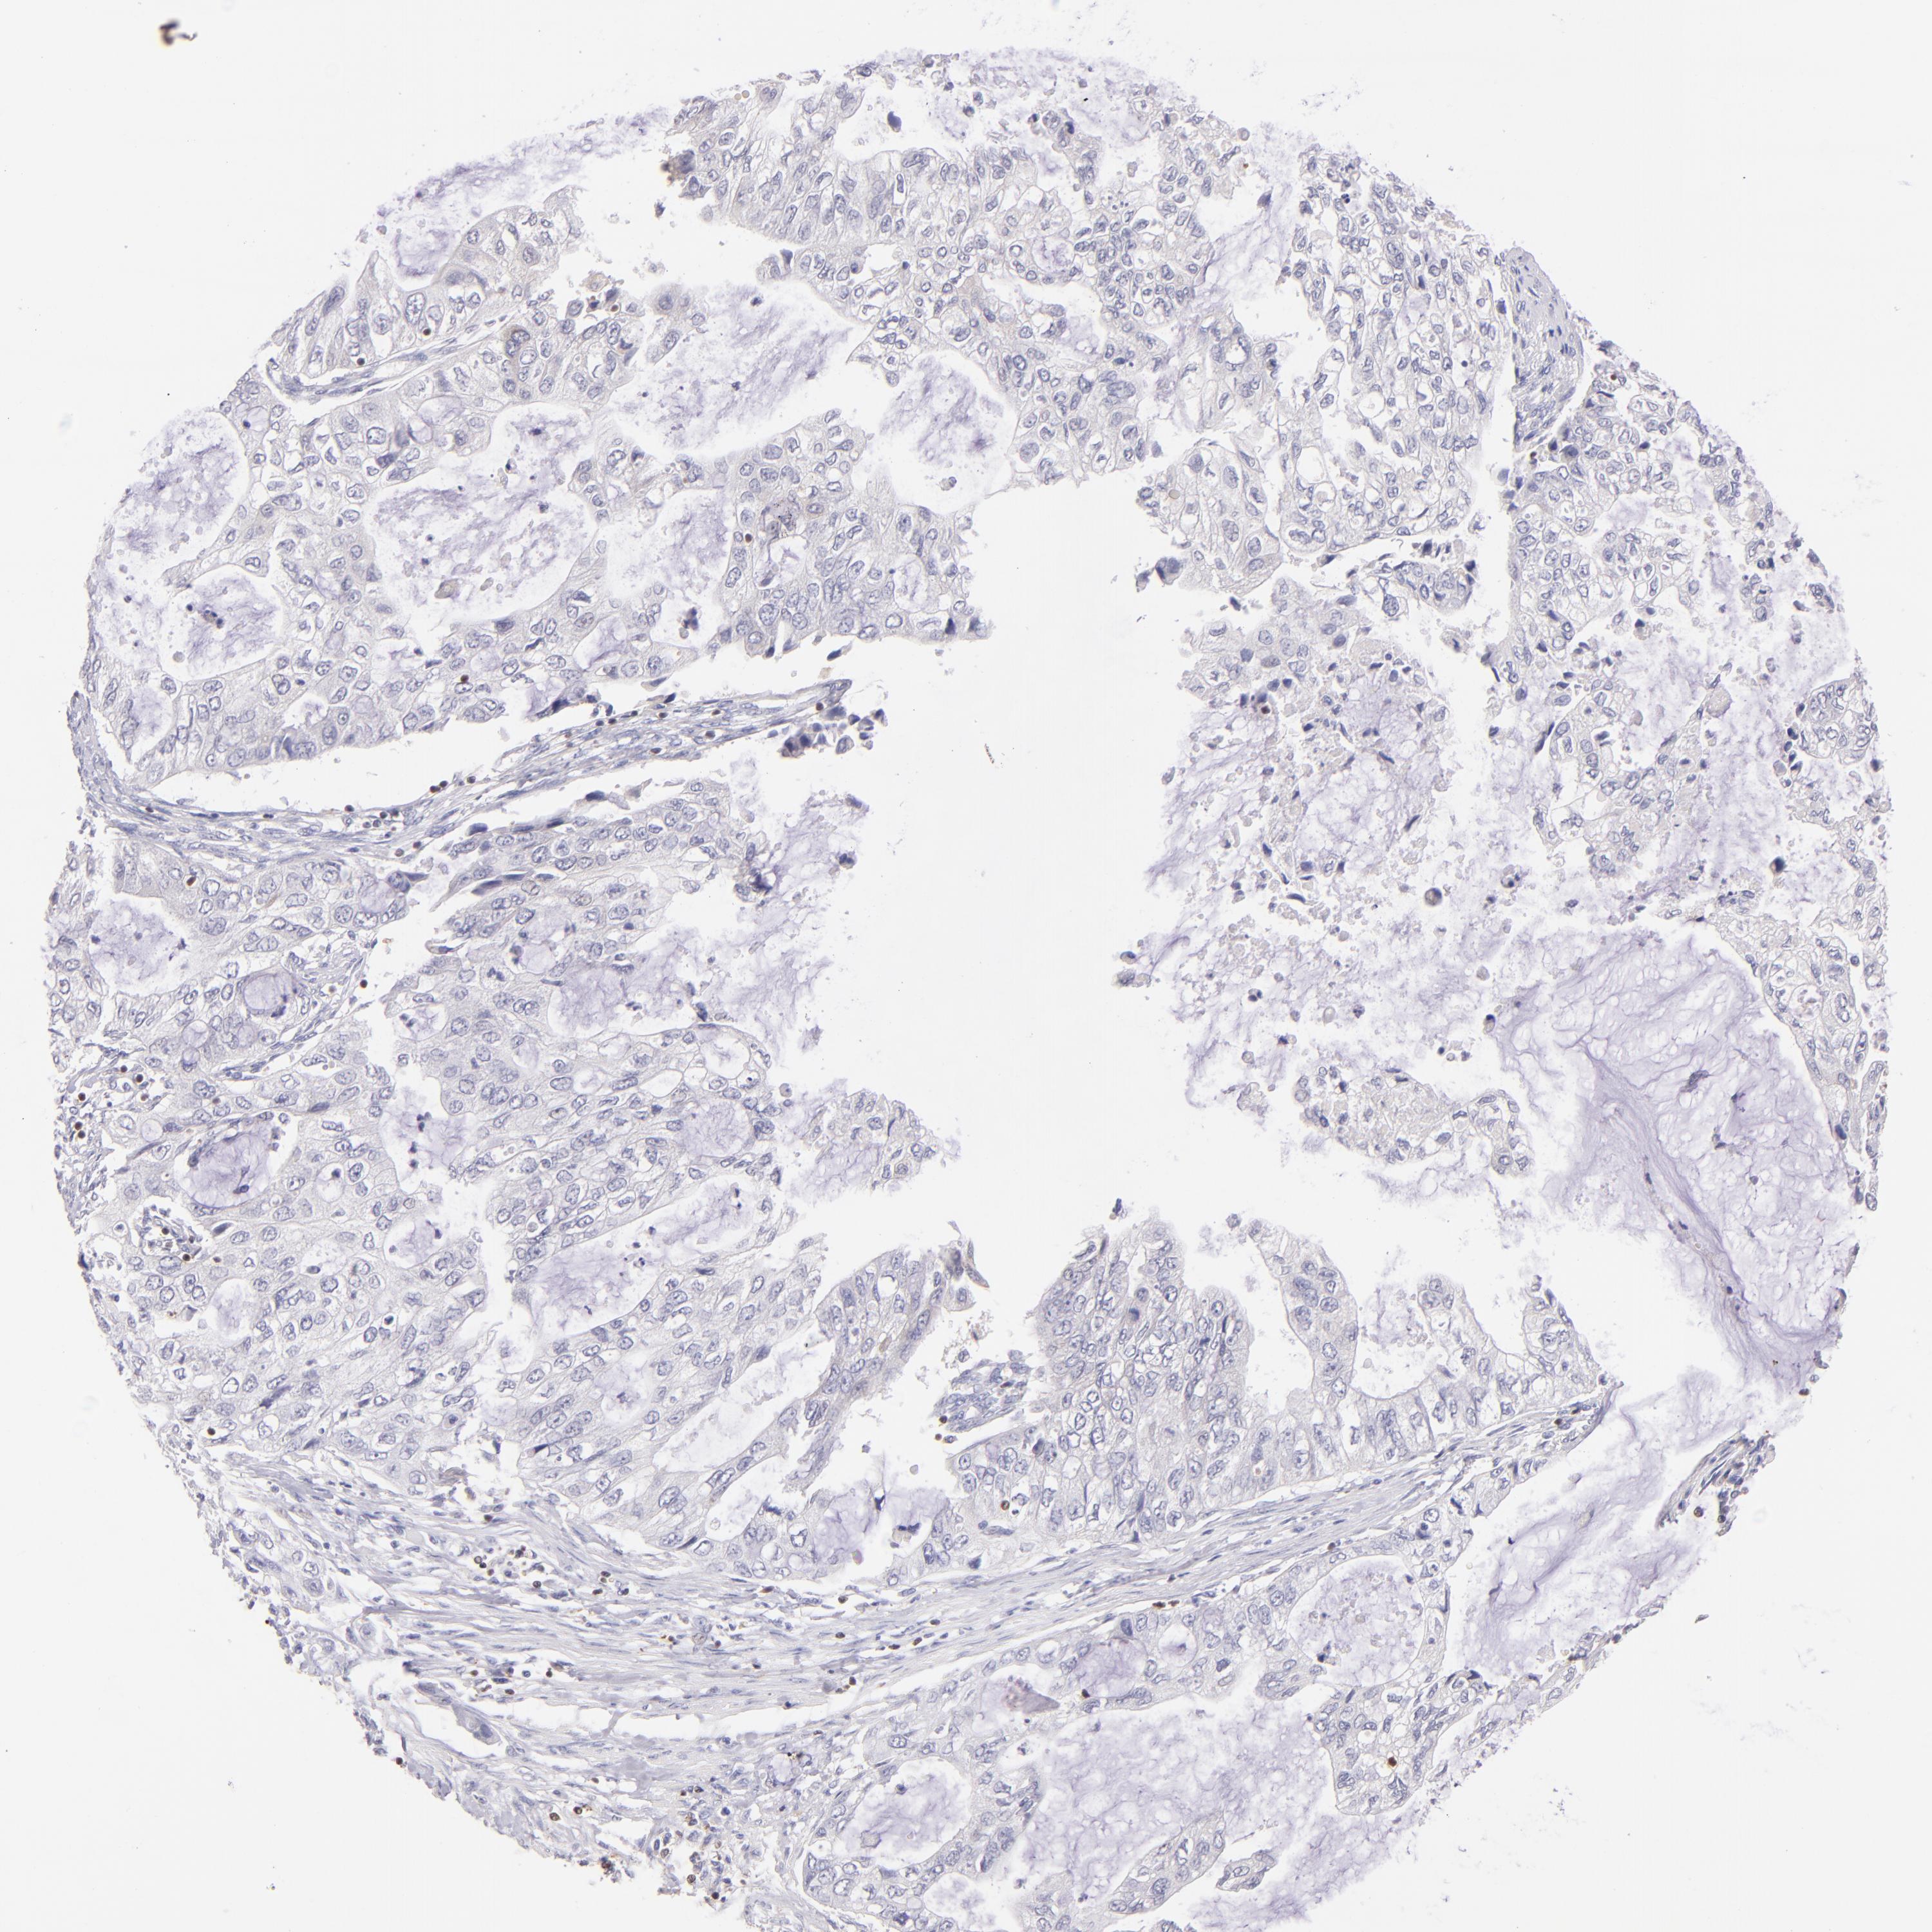

STOMACH CANCER - Protein expressioni

A mouse-over function shows sample information and annotation data. Click on an image to view it in a full screen mode. Samples can be filtered based on level of antibody staining by selecting one or several of the following categories: high, medium, low and not detected. The assay and annotation is described here.

Antibody stainingi

Antibody staining in the annotated cell types in the current human tissue is reported as not detected, low, medium, or high, based on conventional immunohistochemistry profiling in selected tissues. This score is based on the combination of the staining intensity and fraction of stained cells.

Each image is clickable and will lead to virtual microscopy that enables deeper exploration of all samples and also displays staining intensity scores, fraction scores and subcellular localization as well as patient and tissue information for each sample.

Antibody HPA003134

Antibody CAB002625

Staining

High

Medium

Low

Not detected

Intensity

Strong

Moderate

Weak

Negative

Quantity

>75%

75%-25%

<25%

None

Location

Nuclear

Cytoplasmic/membranous

Cytoplasmic/membranous,nuclear

Adenocarcinoma, NOS